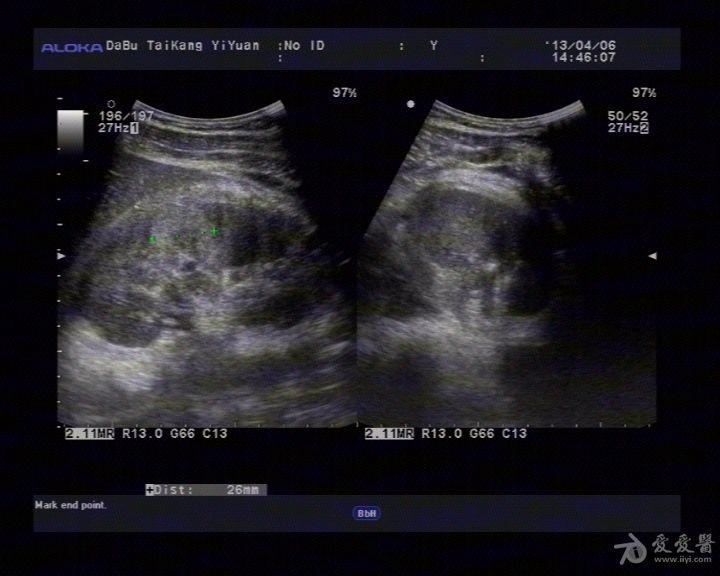

右肾挫裂伤 - 超声医学讨论版 - 爱爱医医学论坛

图片尺寸442x320